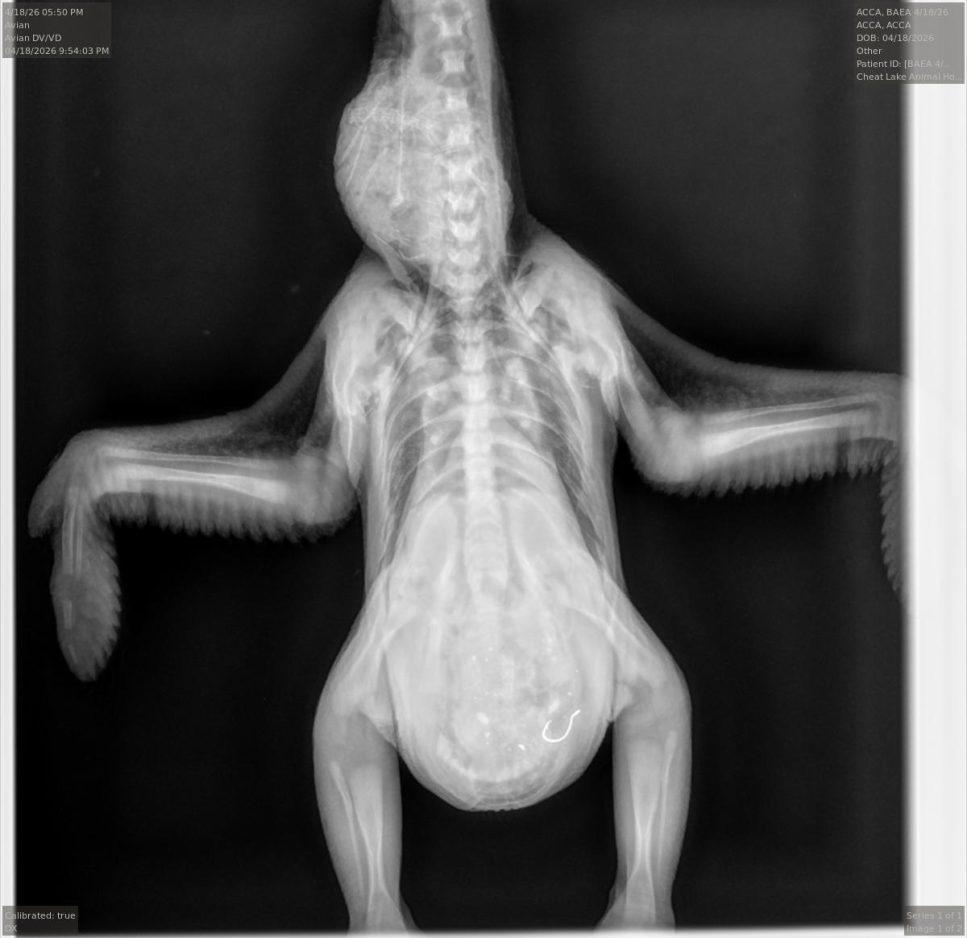

Fallon and his team examined it when it arrived. The bird was quiet and responsive, had the fishing line hanging out of its mouth, but was otherwise in reasonable health for a 2-week-old eagle chick.

They first tried using endoscopy – a camera on a scope – but there was too much food in the bird’s stomach to be able to see the hook.

He made an abdominal incision and removed the hook, which was still attached to the synthetic worm lure and the fishing line. USS11 was out of surgery around 8 p.m., he said.